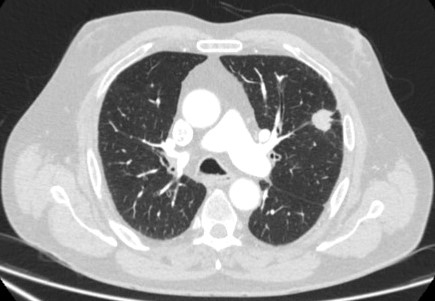

Nódulos sólidos: um tempo de duplicação do volume >600 dias não requer acompanhamento, enquanto um tempo de duplicação do volume <400 dias, ou crescimento nítido definido como um aumento de 25% ou mais no volume, sugere a necessidade de investigações diagnósticas.[Figure caption and citation for the preceding image starts]: Tomografia computadorizada (TC) mostrando nódulo solitário espiculado no lobo superior direito dentro de enfisema, em fumante atual com exposição prévia ao amianto. Observe a placa pleural visível no lado esquerdo. A histologia da ressecção revelou adenocarcinoma do pulmãoDo acervo de Dr. George Tsaknis, MD, PhD, FRCP (Londres), MRQA, MAcadMEd, PGCert; usado com permissão [Citation ends].